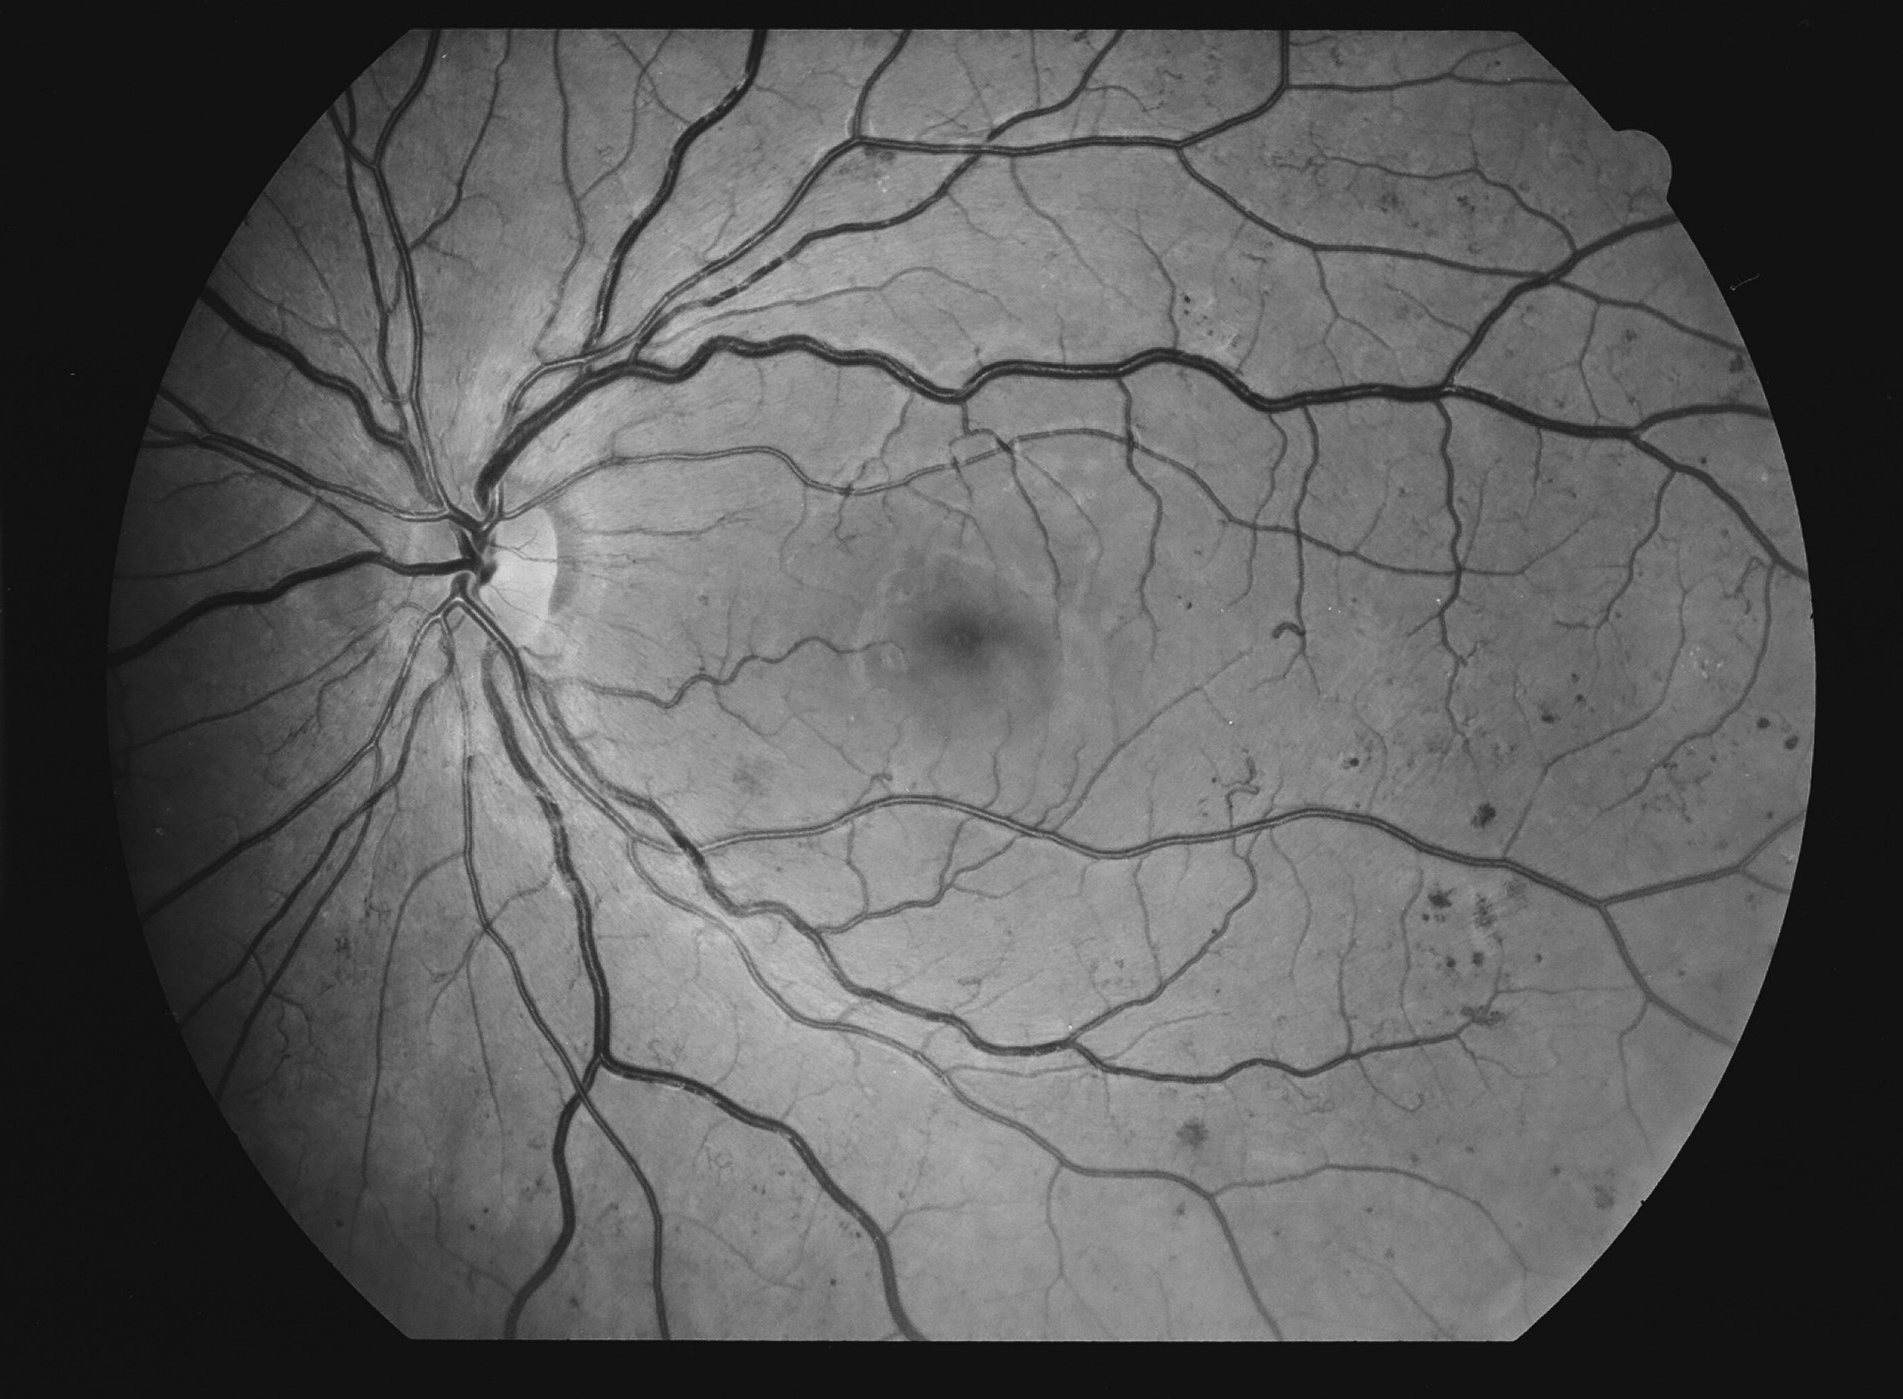

Diabetes, vaikea taustaretinopatia eli preproliferatiivinen retinopatia ja makulopatia, vasen silmä. Mikroaneurysmia, mikroinfarkteja, vuotoja, lipidieksudaatteja ja makulaturvotusta.

Kuva 22.

Diabetes, vaikea taustaretinopatia eli preproliferatiivinen retinopatia ja makulopatia, oikea silmä